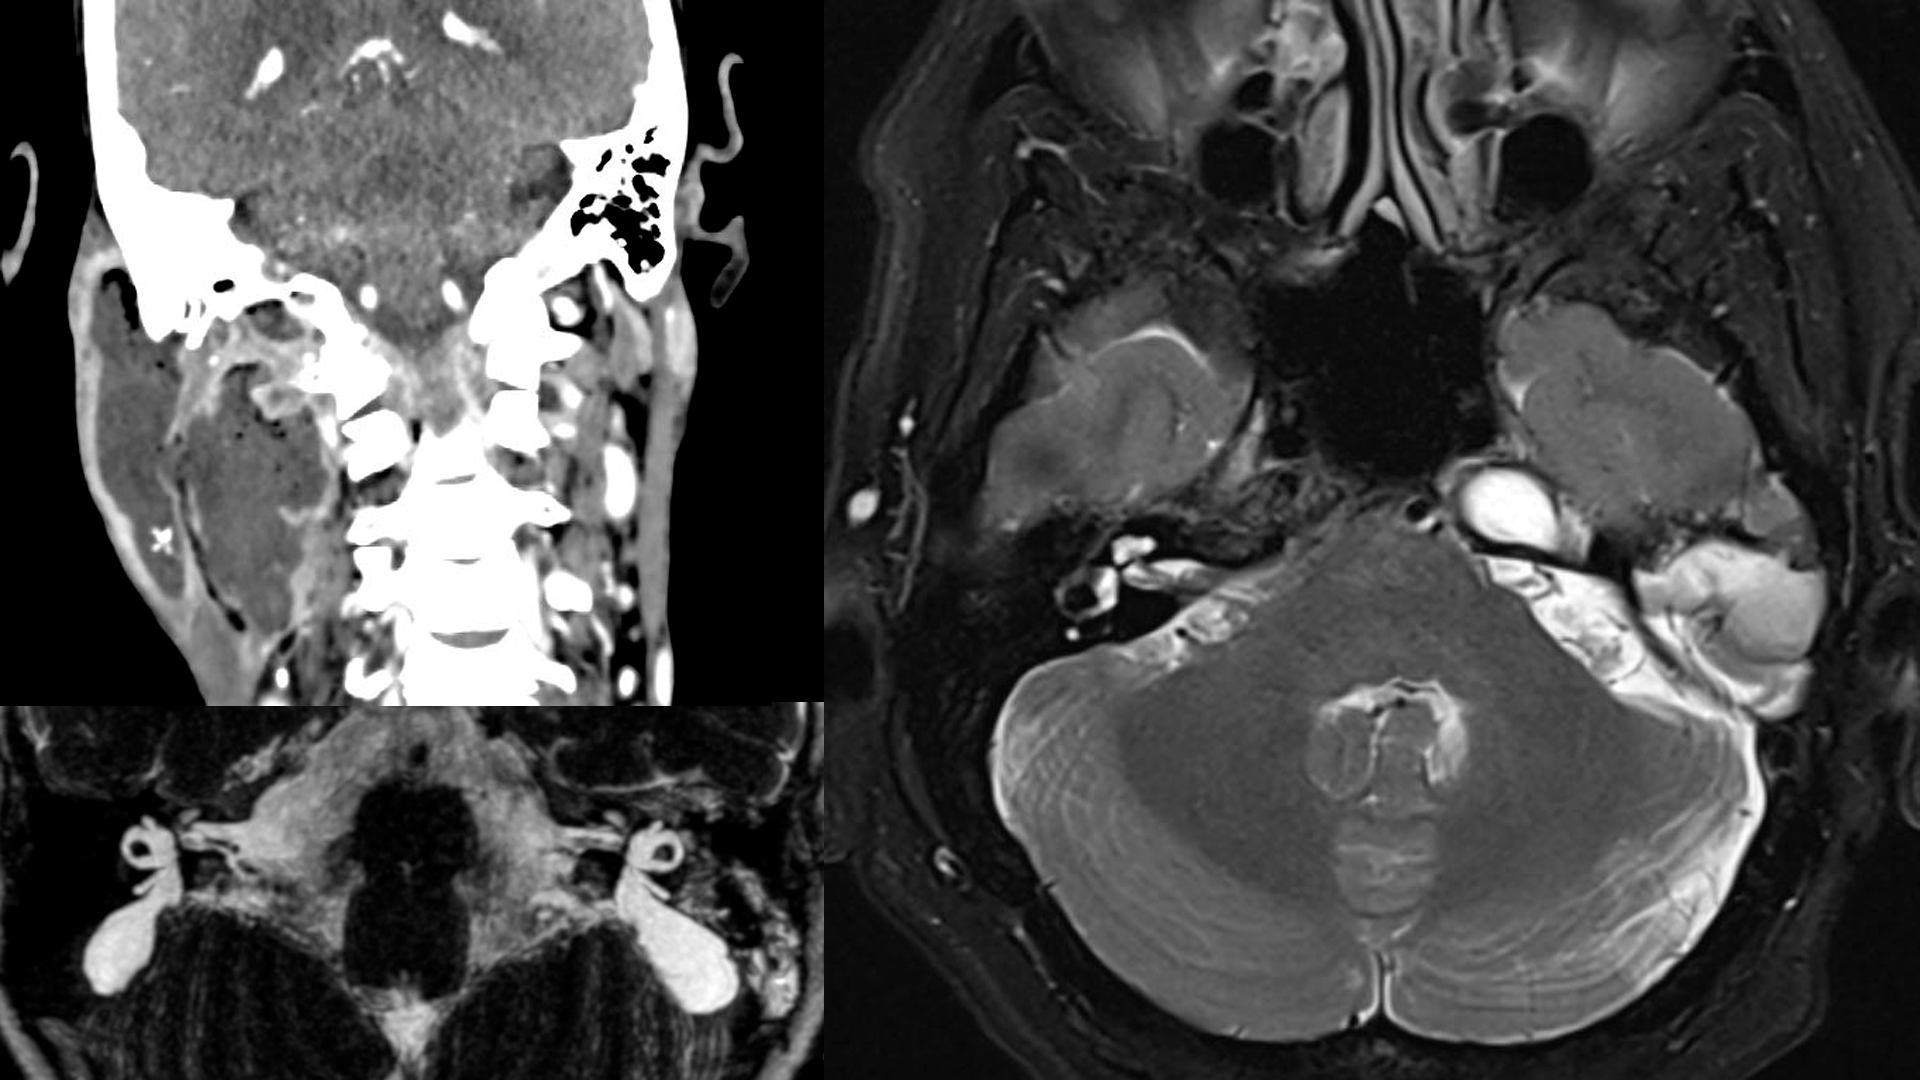

TC e RM de Ossos Temporais:

Tudo o que você precisa saber

• Identificar traumas, inflamações, malformações e tumores